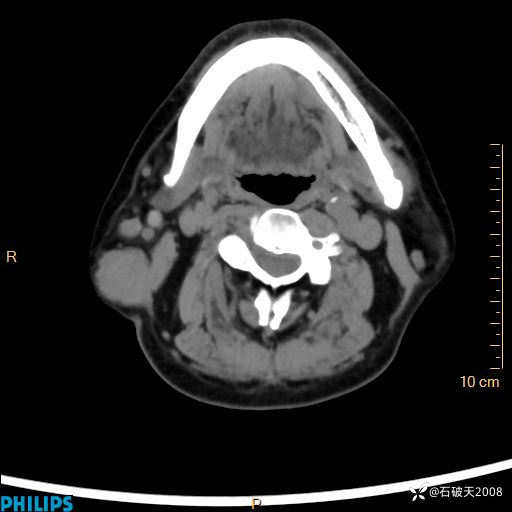

静脉期